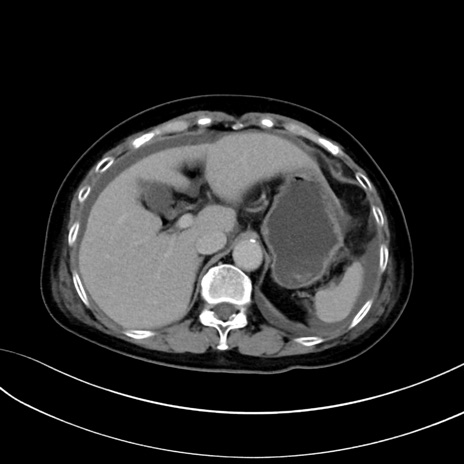

症例13 CT(横断像)1日半後